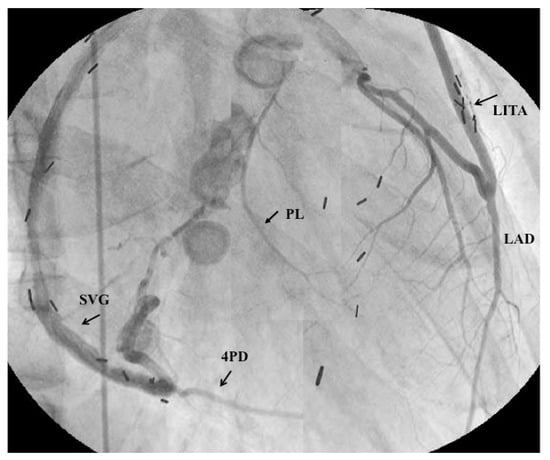

- Tsuda, E.; Kitamura, S.; Kimura, K.; Kobayashi, J.; Miyazaki, S.; Echigo, S.; Yagihara, T. Long-term patency of internal thoracic artery grafts for coronary artery stenosis due to Kawasaki disease: Comparison of early with recent results in small children. Am. Heart J. 2007, 153, 995–1000. [Google Scholar] [CrossRef] [PubMed]

- Tsuda, E.; Kitamura, S. The Cooperative Study of Japan. National survey of coronary artery bypass grafting for coronary stenosis caused by Kawasaki disease in Japan. Circulation 2004, 110 (Suppl. II), II61–II66. [Google Scholar] [CrossRef] [PubMed]

- Kitamura, S.; Tsuda, E.; Kobayashi, J.; Nakajima, H.; Yoshikawa, Y.; Yagihara, T.; Kada, A. Twenty-five-year outcome of pediatric coronary artery bypasss surgery for Kawasaki disease. Circulation 2009, 120, 60–68. [Google Scholar] [CrossRef] [PubMed]